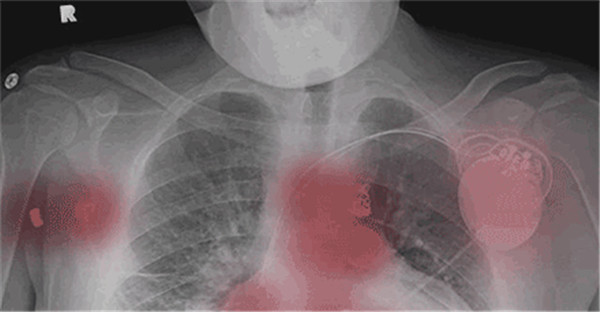

里奇的X光胸片

在人們看來習(xí)以為常的生活空間里,許多新奇好玩的電子產(chǎn)品,如真人CS里的紅外激光戰(zhàn)斗背心、4D電影院的游樂座椅等,對他來說都是無法觸碰的禁忌。

“如果我的設(shè)備突然壞了,我的皮膚下面會響起警報(bào)聲,那一刻,我將充滿對死亡的恐懼。”林奇說。